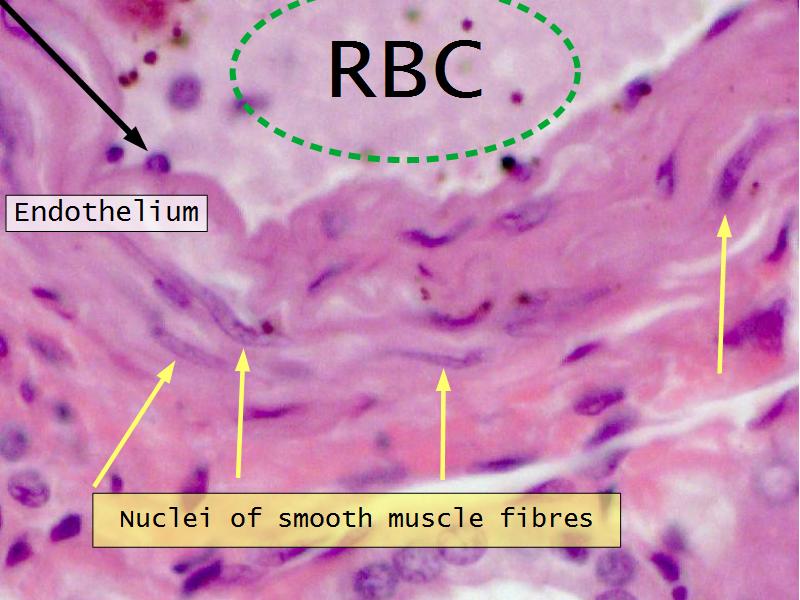

Slides 28 & 76

Kidney: Objectives

- Basic arrangement of nephrons and collecting tubules in the kidney

- Structure of the nephron and collecting tubules

- The renal corpuscle